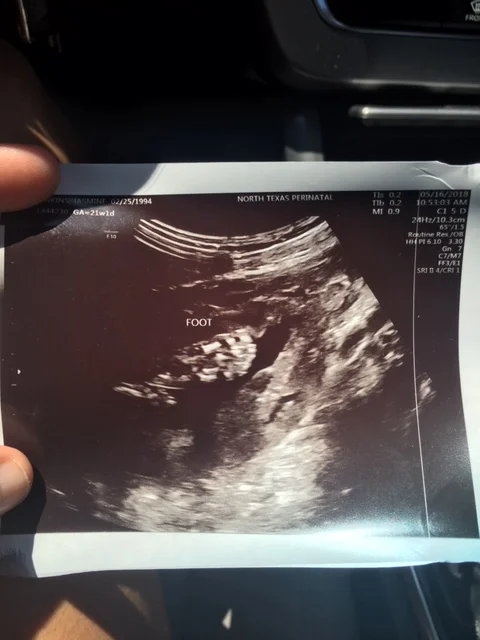

I honestly remember the day like it was yesterday it was May 16, 2018 and I was 21w1d pregnant. It was around 9:00am and my appointment was scheduled for 10:00am. My nephew Trent, who was only 18 months at the time, was with me because my sister got married the day before so I planned to keep him for the week. My boyfriend at the time (now husband) was going to meet us at the doctor’s office from work. We get to the doctor’s office, sign in, and fill out the paperwork. This was a different office than my OBGYN. We wait until my boyfriend arrives. Trent is running around the waiting room doing what toddlers do. Then, my name is called. This is it! For some reason I am super nervous. I ask myself, “For what? I’m just going to see my beautiful baby for the first time.” We go in. I lie down. The ultrasound tech comes in and then next thing you know there he is. DeMarcus Bryson is on the screen! I am in aww. That’s my baby right there on the screen, resting peacefully in mommy’s tummy. Now I am thinking about what it’s going to be like when I have him and how I can’t wait to meet him and kiss him and smell him. All the weird things moms like to do. She showed us his face, hands, feet, arms, legs, and confirmed he was indeed a boy.

Then, she went on to check all of his major organs and make sure they were developing and functioning right. Everything was looking good. We heard his heart beat. It was 166 BPM and he weighed one pound, two ounces. She began taking lots and lots of pictures of his heart. At first, I didn’t think anything of it. She said this was normal as she had to check all of his organs and she had taken pictures of everything else. Mind you, this is my very first child so I don’t really know what is supposed to happen at these things. I’m talking to my boyfriend and playing with my nephew, who was beginning to get antsy because he’s a toddler and we are in a small, dark room with nothing for him to do.

Holding the ultrasound pictures of my little baby and of course the weight of this life-changing news, I couldn’t have imagined I would hear this today. I was so proud of myself for holding it all together, but as soon as I hit the hallway all of the emotions came flooding and I began sobbing.